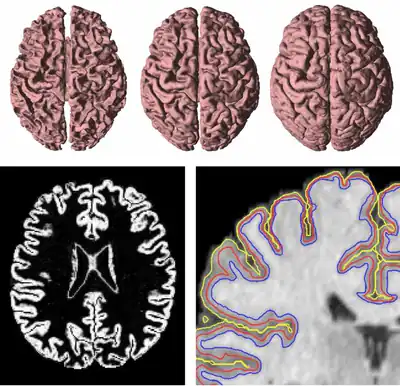

Fig. 4. The inner, central, and outer surfaces of the human brain cortex (top) are found sequentially using GVF forces in three geometric deformable models. The central surface uses the gray matter membership function (bottom left) as an edge map itself, which draws the central surface to the central layer of the cortical gray matter. The positions of the three surfaces are shown as nested surfaces in a coronal cutaway (bottom right).

GVF has been used to find both inner, central, and central cortical surfaces in the analysis of brain images,[5] as shown in Figure 4. The process first finds the inner surface using a three-dimensional geometric deformable model with conventional forces. Then the central surface is found by exploiting the central tendency property of GVF. In particular, the cortical membership function of the human brain cortex, derived using a fuzzy classifier, is used to compute GVF as if itself were a thick edge map. The computed GVF vectors point towards the center of the cortex and can then be used as external forces to drive the inner surface to the central surface. Finally, another geometric deformable model with conventional forces is used to drive the central surface to a position on the outer surface of the cortex.